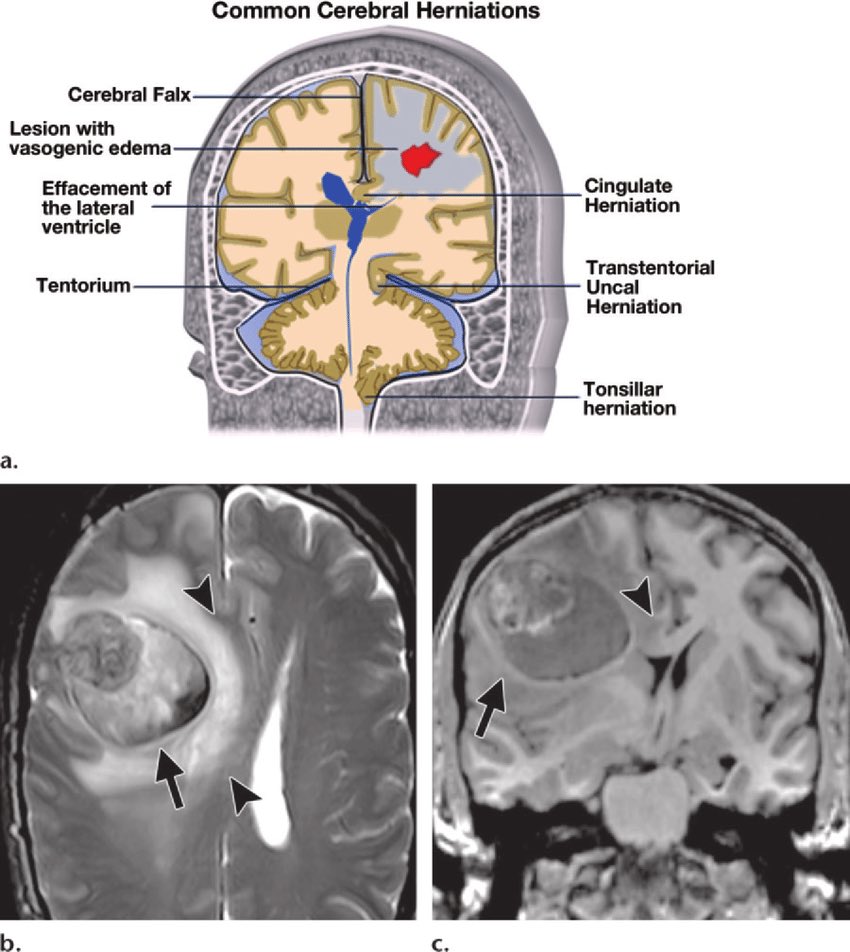

▫️Herniation of the brain 🧠🌟

✳️ Midline shift➕herniation